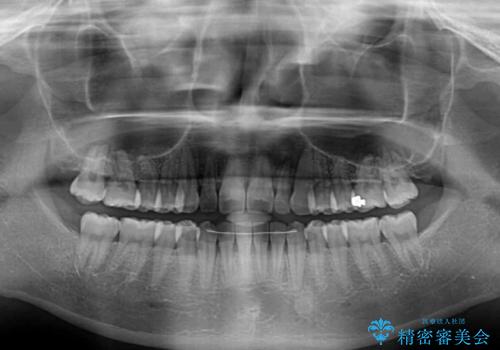

すきっ歯とオープンバイトをインビザラインで改善

- 前歯の上下スペースと前歯の隙間を気にして来院された患者様です。

インビザラインにより上下の前歯の隙間を閉じていくこととしました。

上下の隙間に舌が入り込むことが、すきっ歯やオープンバイトの原因であったため、舌の筋肉のトレーニングも並行して行い、後戻りの抑制を図りました。